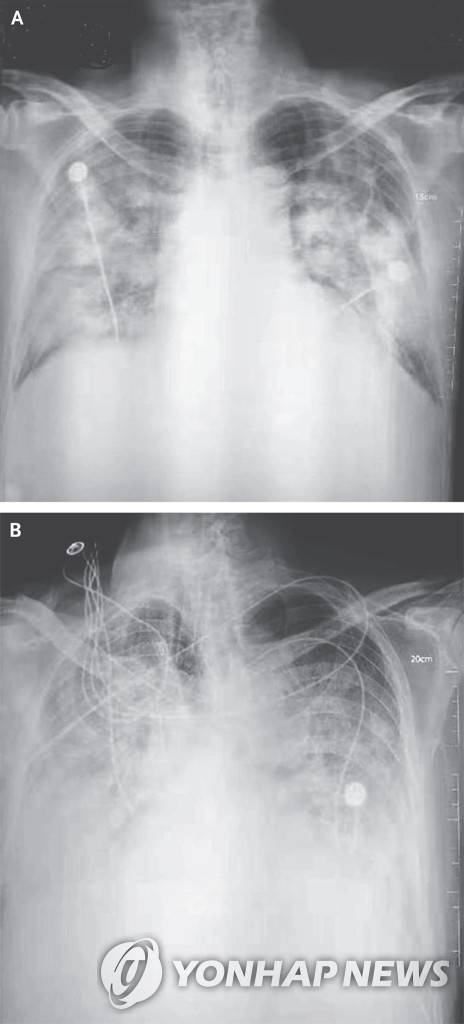

![우한 폐렴 환자의 흉부 방사선 사진 [NEJM 논문 발췌]](https://img2.daumcdn.net/thumb/R658x0.q70/?fname=https://t1.daumcdn.net/news/202505/13/yonhap/20250513060022975hsbu.jpg)

이번에 도입되는 AI 기술은 만 19세 이상 흉부 질환 의심 환자를 대상으로 한다. 환자가 병원에서 일반적인 방식(후전위 또는 전후위 자세)으로 가슴 X선 촬영을 하면, AI 알고리즘이 이 영상을 분석해 폐에 이상 소견이 있는지, 있다면 어느 위치에 있는지를 의료진에게 알려준다.

AI가 검출할 수 있는 이상 소견은 ▲ 결절(폐에 생긴 작은 혹) ▲ 경화(폐 조직 일부가 딱딱하게 굳는 현상) ▲ 간질성 음영(폐 조직 사이의 공간에 이상이 생겨 X선 영상에서 비정상적으로 보이는 부분) ▲ 흉막삼출(폐를 둘러싼 막 사이 공간에 물이 차는 현상) ▲ 기흉(폐에 구멍이 생겨 공기가 새어 나오는 상태) 등 5가지 주요 질환이다.